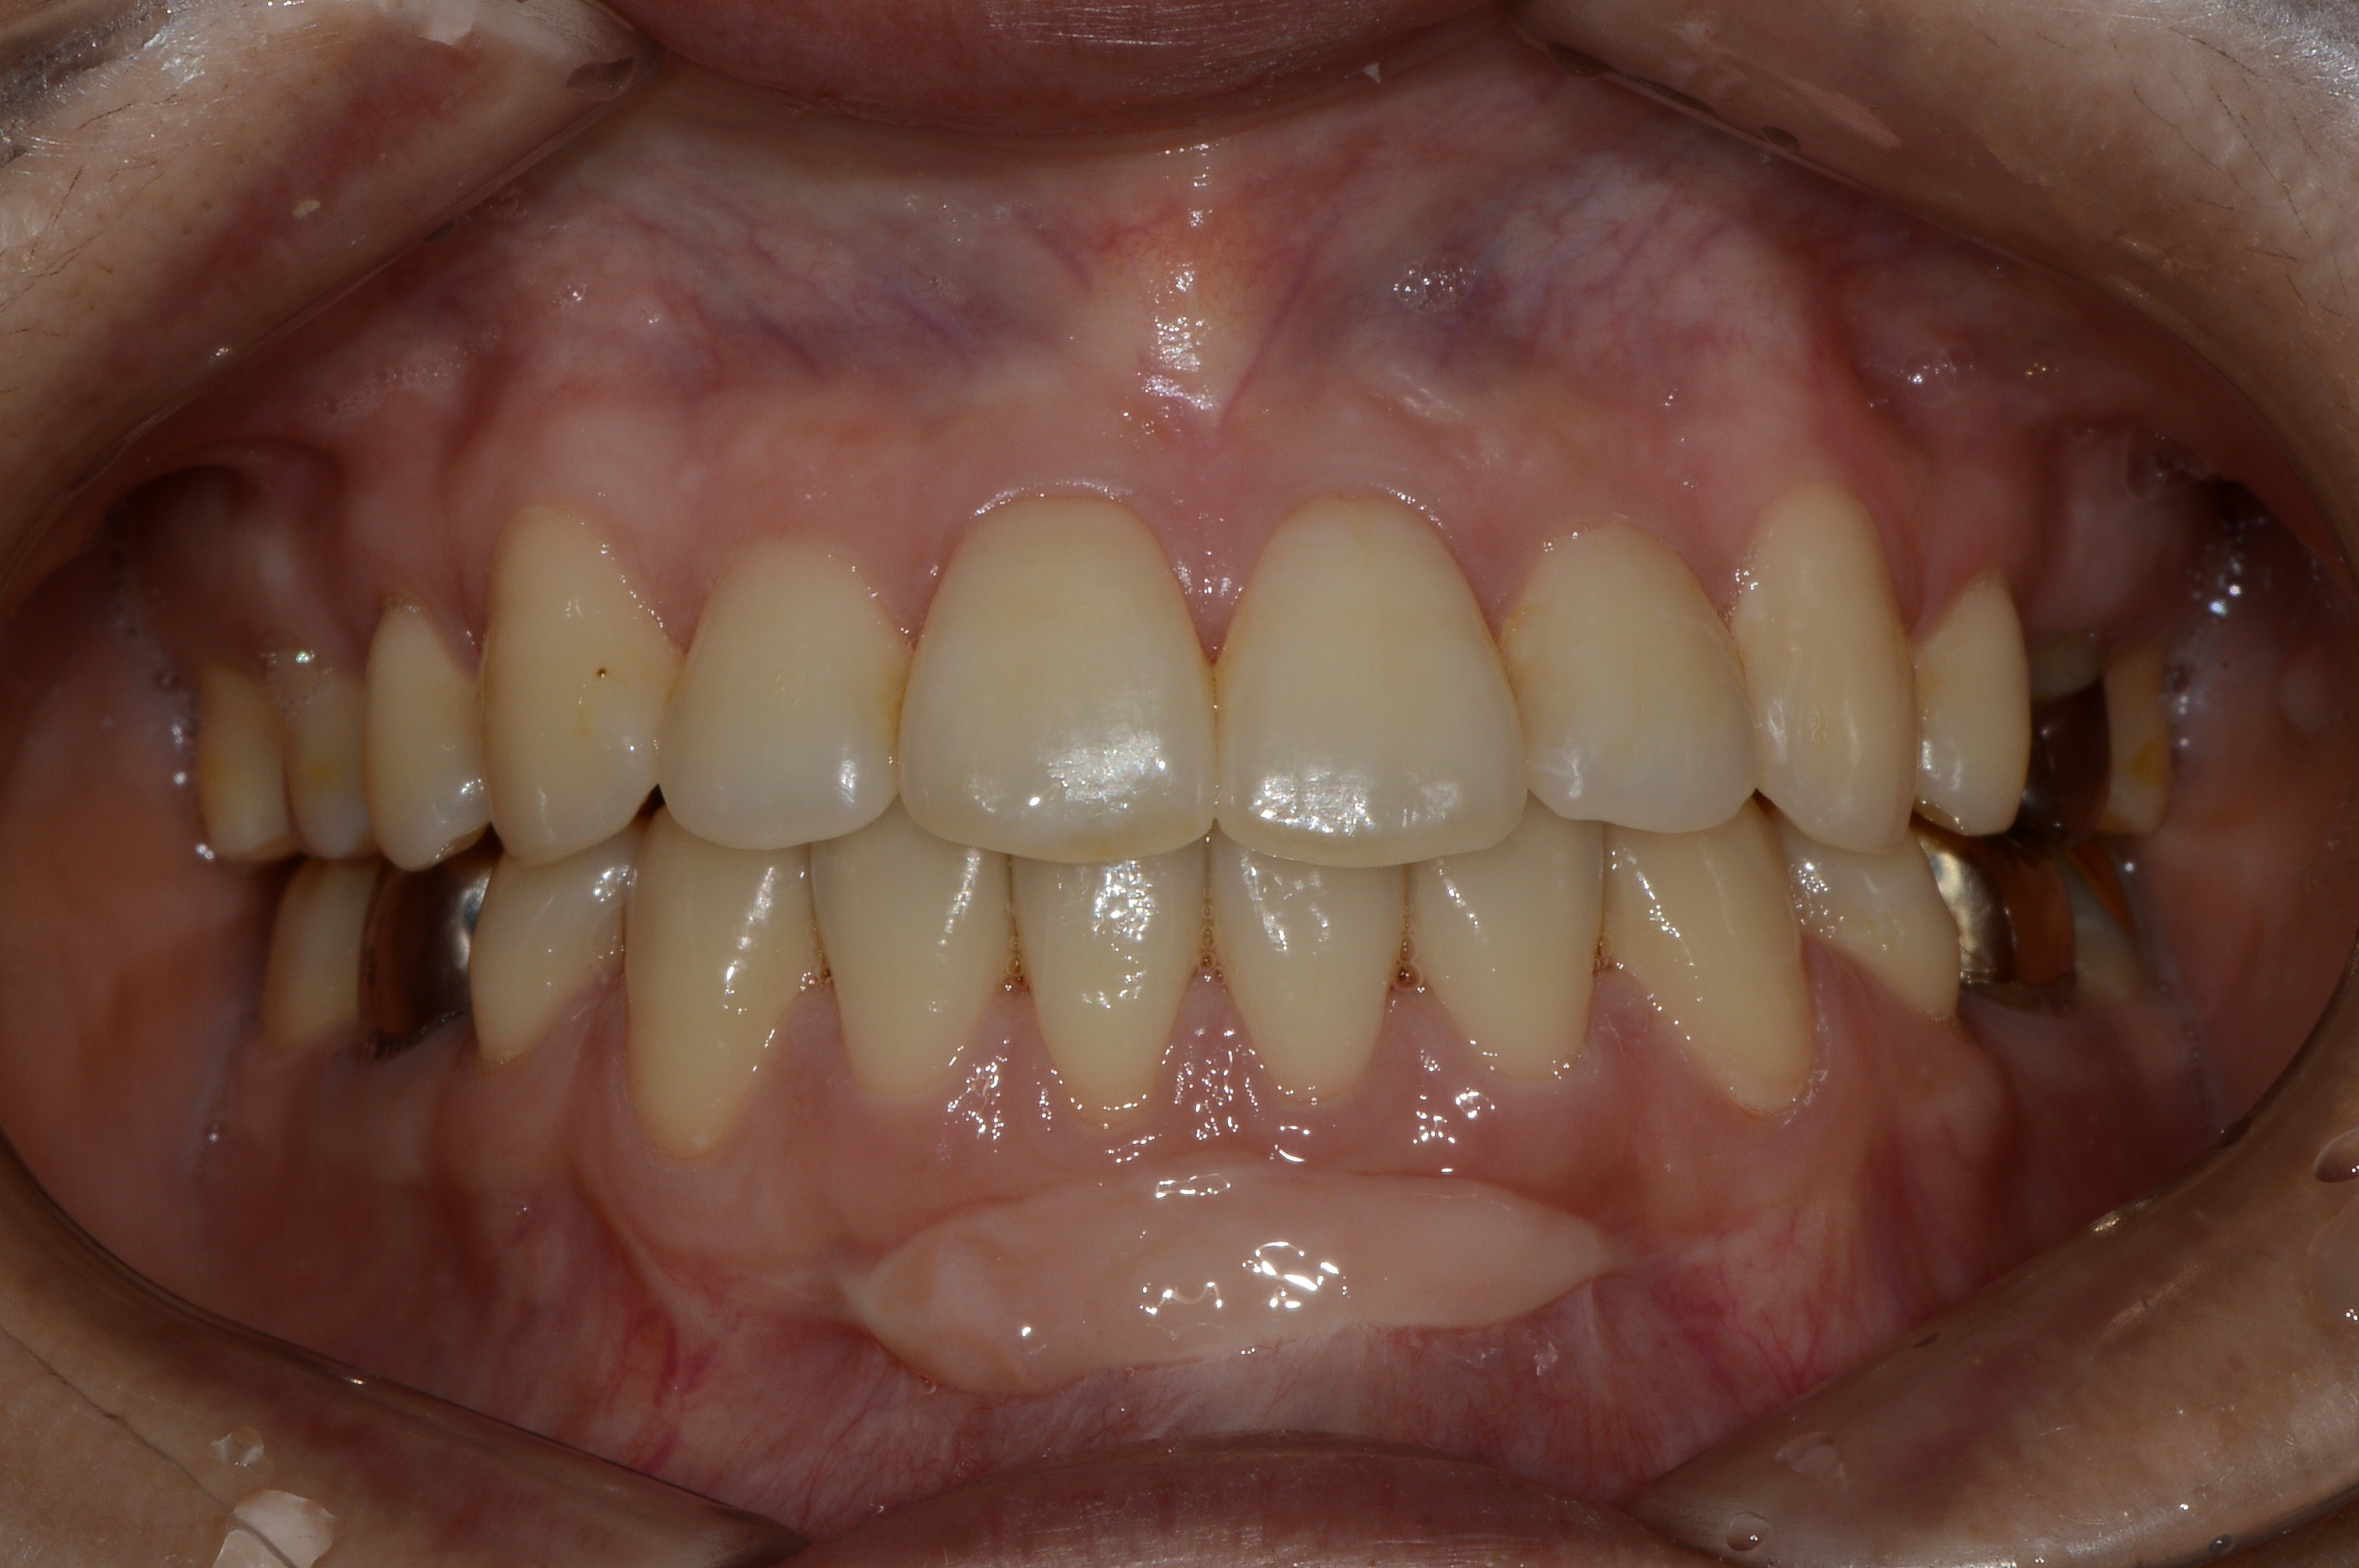

치료 전 사진입니다.